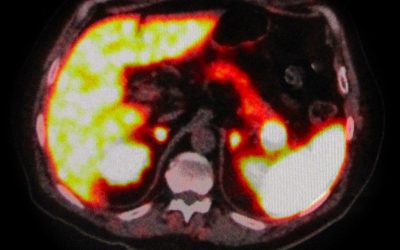

Nodulo intra-pancreatico non metastatico evidenziabile con RMN e 68Ga-DOTA-peptide PET/TC: resezione pancreatica o agobiopsia eco-endoguidata?

di Enrico Ganz l riscontro accidentale di un isolato nodulo intrapancreatico non metastatico nel corso di una tomografia computerizzata (TC) pone il problema di comprendere se sia opportuno un trattamento chirurgico, un periodico controllo della lesione o...